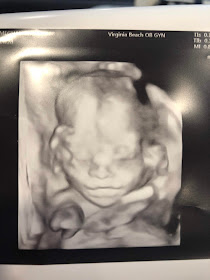

Aside from finding out about her gender, baby #3 appears to be healthy and growing nicely. She is in the 50th percentile, which seems about right for my babies, and I think her side profiles look a lot like Lilly's did.